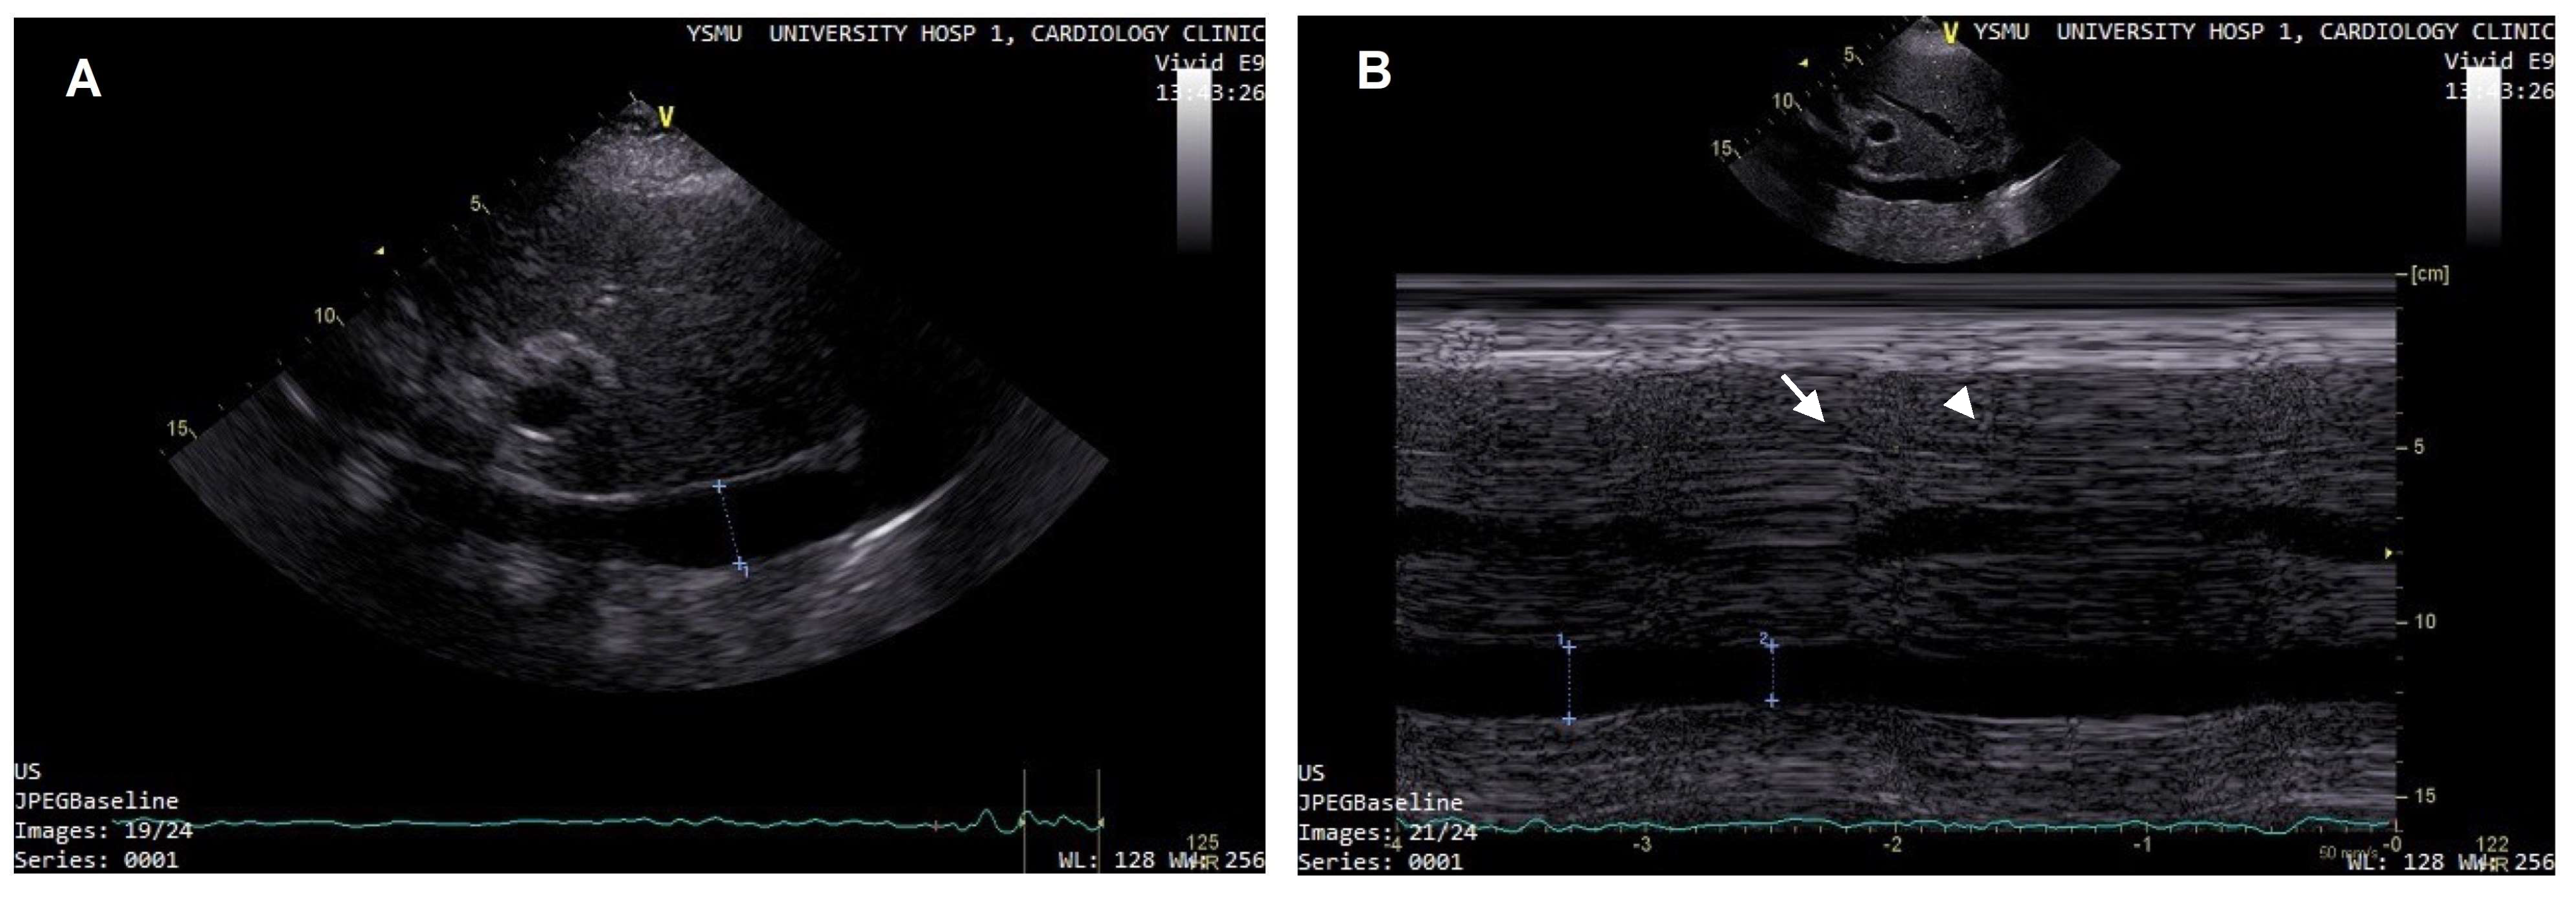

- Pellicori, P.; Carubelli, V.; Zhang, J.; Castiello, T.; Sherwi, N.; Clark, A.L.; Cleland, J.G. IVC Diameter in patients with chronic heart failure: Relationships and prognostic significance. JACC Cardiovasc. Imaging 2013, 6, 16–28. [Google Scholar] [CrossRef]

- Kircher, B.J.; Himelman, R.B.; Schiller, N.B. Noninvasive estimation of right atrial pressure from the inspiratory collapse of the inferior vena cava. Am. J. Cardiol. 1990, 66, 493–496. [Google Scholar] [CrossRef]

- Nath, J.; Vacek, J.L.; Heidenreich, P.A. A dilated inferior vena cava is a marker of poor survival. Am. Heart J. 2006, 151, 730–735. [Google Scholar] [CrossRef]

- Curbelo, J.; Rodriguez-Cortes, P.; Aguilera, M.; Gil-Martinez, P.; Martín, D.; Suarez Fernandez, C. Comparison between inferior vena cava ultrasound, lung ultrasound, bioelectric impedance analysis, and natriuretic peptides in chronic heart failure. Curr. Med. Res. Opin. 2019, 35, 705–713. [Google Scholar] [CrossRef]

- Curbelo, J.; Aguilera, M.; Rodriguez-Cortes, P.; Gil-Martinez, P.; Suarez Fernandez, C. Usefulness of inferior vena cava ultrasonography in outpatients with chronic heart failure. Clin. Cardiol. 2018, 41, 510–517. [Google Scholar] [CrossRef] [PubMed]

- Lee, H.F.; Hsu, L.A.; Chang, C.J.; Chan, Y.H.; Wang, C.L.; Ho, W.J.; Chu, P.H. Prognostic significance of dilated inferior vena cava in advanced decompensated heart failure. Int. J. Cardiovasc. Imaging 2014, 30, 1289–1295. [Google Scholar] [CrossRef]